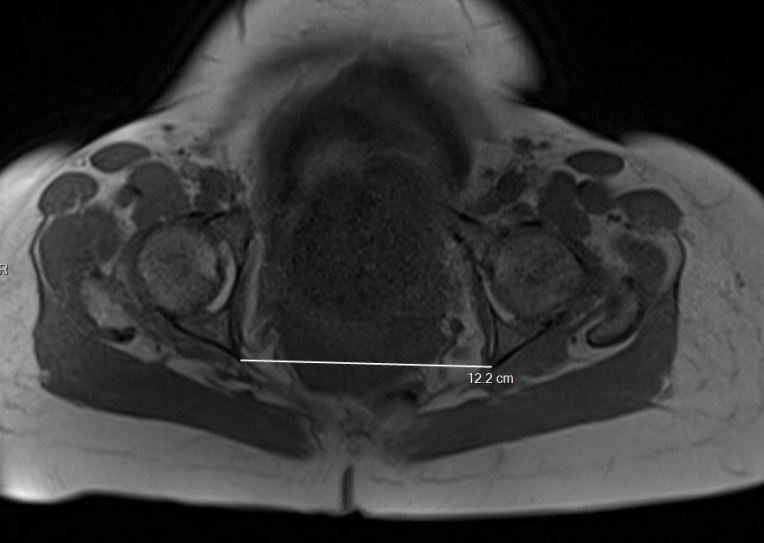

Sur les coupes transverses :

- Sur la coupe passant par les ischions, la distance intertubéreuse, la distance la plus large entre les tubérosités ischiatiques ;